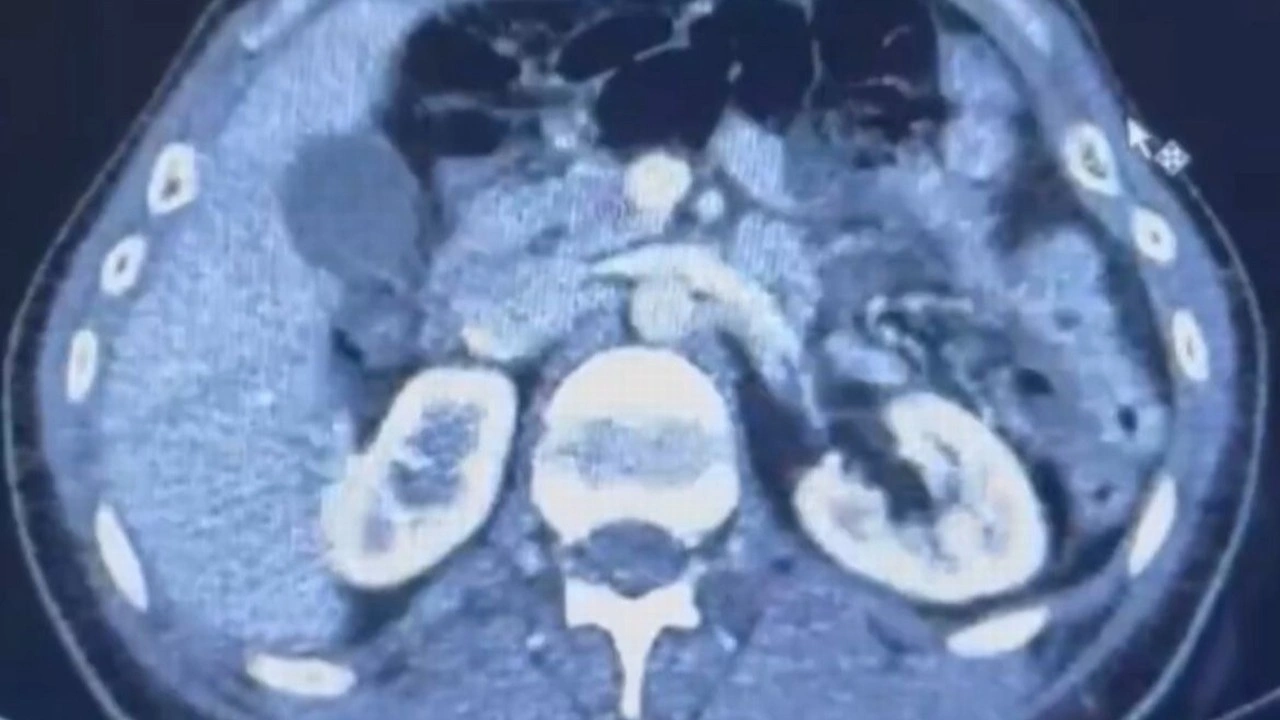

Şüphelilerden S.C. ve R.B.C. muayene edilmek üzere Kayseri Şehir Hastanesi'ne getirildi.

Röntgeni ve ultrason çekilen şüphelilerin midesinde yaklaşık 50 kapsülde 554 gram uyuşturucu olduğu tespit edildi.

Uyuşturucular sağlık ekiplerinin tedavisiyle çıkarıldı. 3 şüphelinin emniyetteki işlemleri ise sürüyor.